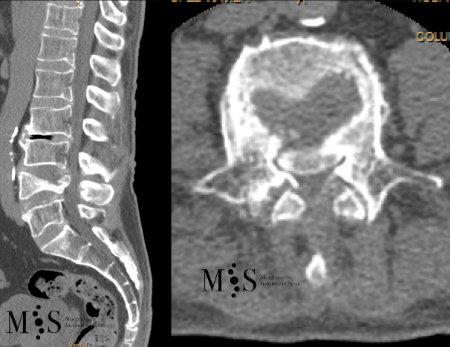

Estabilització percutània de fractures vertebrals inestables

En casos de fractures vertebrals complexes, inestables, comminutes, etc. es requereix una estabilització addicional de la fractura mitjançant una artròdesi percutània, i en alguns casos en els quals hi ha compromís neurològic, una descompressió del canal medul·lar. L’artrodesi percutània permet estabilitzar l’estructura compromesa de la columna vertebral i descarregar la càrrega del pacient sobre la fractura. Addicionalment se solen cementar les vertebres artròdesis i la fractura vertebral mitjançant cifoplastia.

Fractura Vertebral Ejemplo de Caso Clínico

En els casos de les fractures més greus, com les fractures conminutes i les fractures d’esclat, un fragment del cos vertebral pot ficar-se dins del canal medular, provocant una compresió de les estructures neurològiques (estenosi del canal medular).

Quan amés n’hi ha un compromis neurològic, s’haruá de realitzar una resecció parcial o total del cos vertebral fracturat (corpectomia) per després reconstruir-lo reconstrucción mitjantçant d’una caixa somàtica expandible. La reconstrucció es sol completar amb una artrodesi percutànea instrumentada i cementada dels nivells adjacents a la fractura. La resecció de la vèrtebra (corpectomia) permet extrahir el fragment d’os qu’es trova al canal medular i lliberar les estructures neurològiques afectades. La reconstrucció amb una caixa somàtica permit descarregar la carga del pacient sobre la fractura i treure el dolor que aquesta li provoca.

Cas clínic d'una resecció (corpectomia) i reconstrucció vertebral lumbar en una fractura esclat de nivell L4.